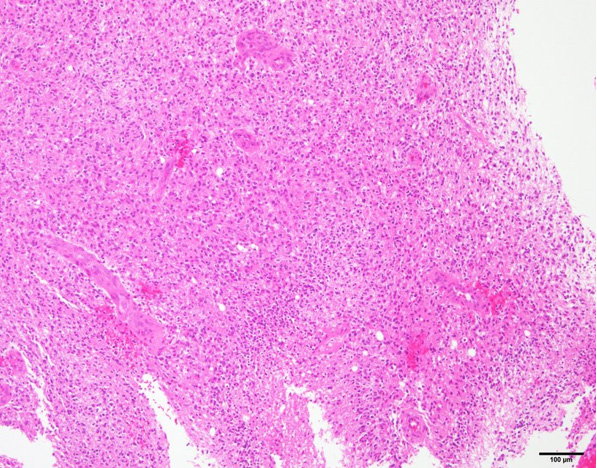

病理組織所見

• 11C-methionine PET(非提示)で高集積を認めた左頭頂葉深部白質の病変に対して定位脳腫瘍生検を施行した。

• 組織学的には、核形不整のある異型グリア細胞が密度高く増生し、一部に壊死巣があり偽柵状配列を辺縁に伴っていた。また一部に内皮細胞の腫大を伴う血管増生を認めた。核分裂像数は23/10 high power fields。

• 免疫染色では、GFAP:陽性、Olig2:陽性、IDH1:陰性、MGMT:多数に弱陽性で、強陽性も散見される、p53:少数に陽性、Ki-67陽性率:25.6% であった。

上記より、Glioblastoma, WHO Grade IVの診断となった。

• HE染色 弱拡大